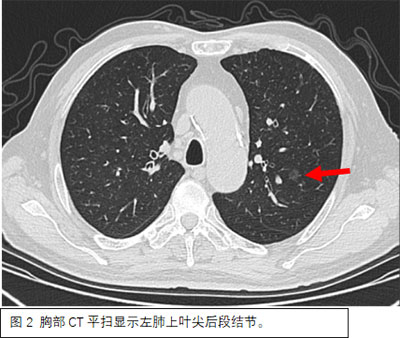

患者因体检发现肺部阴影到北京胸科医院就诊治疗。据胸外一科主任阮军忠介绍,患者左肺有2个需要治疗的高危结节,大者位于左肺下叶背段,最大径达30mm(图1),另一个结节位于左肺上叶尖后段,直径为8mm(图2);同时,患者高龄75岁,合并多年高血压、冠心病、糖尿病史。若均通过外科手术切除高危结节,则会损失较多肺功能,且手术创伤大、时间长,围术期心血管事件风险明显升高。根据患者病情,胸外一科阮军忠团队与CT介入科主任侯代伦及副主任医师王东坡团队联合进行了术前讨论和准备,并与患者家属充分沟通后,制定了治疗方案,决定在同一天,先由王东坡团队于放射科局麻下行CT引导下经皮穿刺微波消融手术治疗左肺上叶尖后段结节(图3),随后由阮军忠团队于手术室全麻下行胸腔镜下左肺下叶背段切除术(图4)。